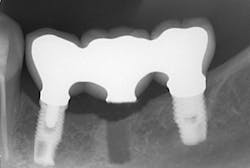

The same arguments have been advanced for not splinting adjacent implants in segmental reconstructions (figure 1). Plaque-related peri-implantitis is the most common biological complication in implant dentistry. A passive fit of prostheses on their supporting implants is considered essential for minimizing mechanical and biological overloading. On the other hand, it is also claimed that splinting can prevent overloading (figure 2). Screw loosening and fracture of veneering material are the most common mechanical complications of loading, although there is little evidence that it results in loss of integration.

Figure 1: Nonsplinted adjacent implants